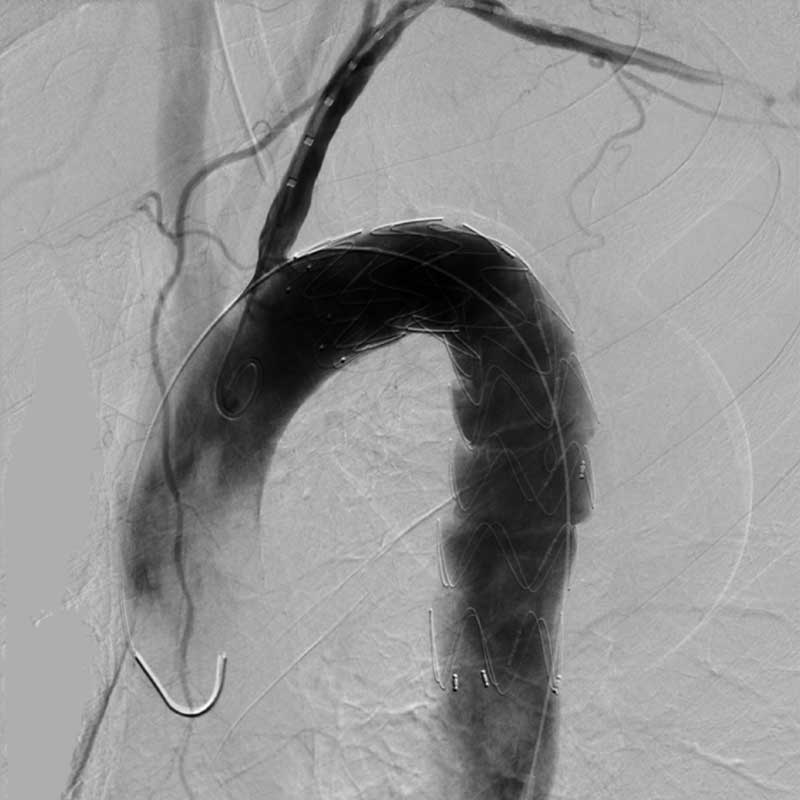

Wir versorgen die ambulanten und stationären Patientinnen und Patienten des Evangelischen Krankenhauses Göttingen-Weende an seinen Standorten mit modernsten bildgebenden Verfahren. Hierzu nutzen wir das gesamte Spektrum der radiologischen Diagnostik – volldigitales Röntgen, Durchleuchtung sowie Sonographie, Computertomographie (CT), Kernspintomographie (MRT) und Digitale Subtraktionsangiographie (DSA). Wir kooperieren eng mit unseren klinischen Fachbereichen und den Kliniken der Universitätsmedizin Göttingen. Zusätzlich sind wir bundesweit mit einer Vielzahl externer Spezialistinnen und Spezialisten vernetzt.

• Kardiovaskuläre Radiologie: Dr. J. Gossner, Prof. C. Engelke

• Endovaskulär-minimalinvasive Therapieverfahren: Prof. C. Engelke

• Interdisziplinäre Diagnostik und Therapie seltener Gefäßerkrankungen: Prof. C. Engelke